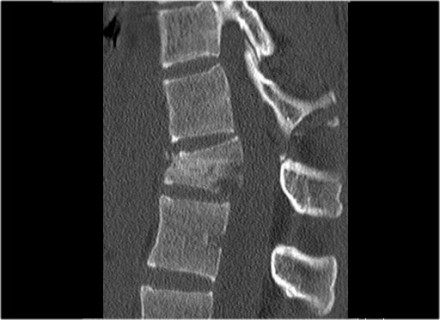

Look at the images.

How would you describe the morphology and the PLC?

The findings are:

- Morphology: Translation - 3 points

- PLC: always disrupted in translation - 3 points

- TLICS: 6 points